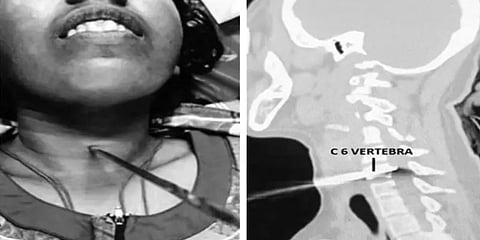

கடந்த 22-8-22 அன்று 28 வயது மதிக்கத்தக்க இளம் பெண் ஒருவரின் கழுத்தின் முன் பகுதியில் இரும்பு கம்பி ஒன்று குத்தப்பட்ட நிலையில் கை கால்கள் செயலிலழந்தது. இந்நிலையில், கோவை அரசு மருத்துவமனை அவசர சிகிச்சை பிரிவில் அனுமதிக்கப்பட்டார். பெண்ணிற்கு வலிப்பு வந்தபோது அவர் கையில் கொடுக்கப்பட்ட கம்பி கழுத்தில் குத்தியதாக அவருடன் வந்த உறவினர்கள் தெரிவித்துள்ளனர்.

இதையடுத்து ஸ்கேன் மற்றும் இதர பரிசோதனை முடிவில் கழுத்தில் வலது பக்கம் பாய்ந்த கம்பி மூச்சுக் குழாய் உணவு குழாய் மற்றும் ரத்த நாளங்களில் மிக அருகில் பாய்ந்து தண்டுவட எலும்பை துளைத்து குத்தி இருப்பது தெரியவந்தது. இதைத் தொடர்ந்து மருத்துவமனை முதல்வர் நிர்மலா அவர்களின் ஆலோசனைப்படி நரம்பியல் அறுவை சிகிச்சை, இதய அறுவை சிகிச்சை மற்றும் மயக்க மருந்து நிபுணர்கள் ஆகியோர் பெண்ணிற்கு அறுவை சிகிச்சை செய்து கழுத்தில் பாய்ந்த கம்பியை எந்தவித பாதிப்பும் இன்றி அகற்றினர்.